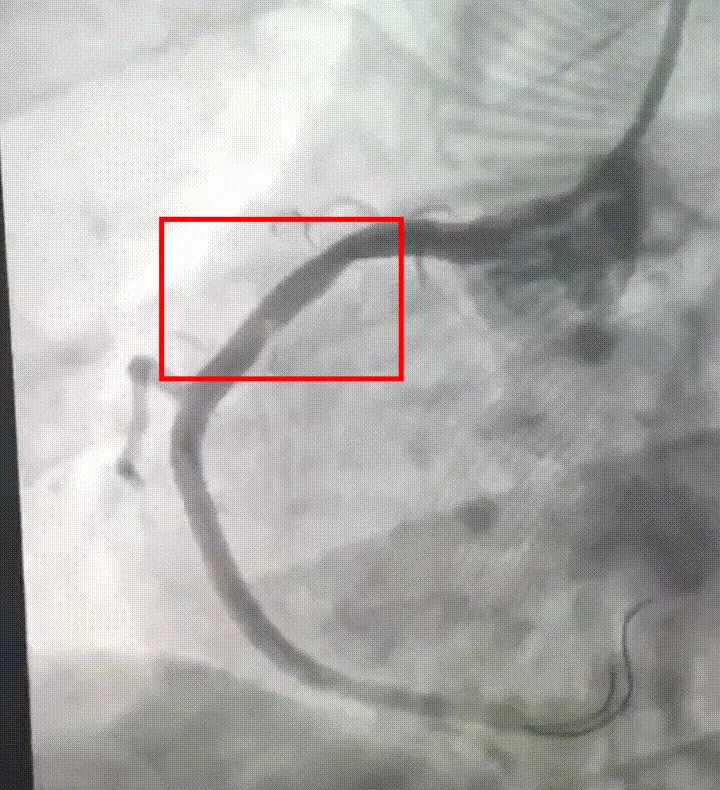

很快,该院心内科团队迅速到位。楼善杰主任医师通过冠脉造影检查发现小王右冠状动脉近端被大量血栓完全闭塞。这条负责心脏重要区域供血的主要血管血流中断,心肌面临持续损伤风险,救治刻不容缓。

急诊经皮冠状动脉介入治疗(PCI)随即在导管室展开。在血管造影设备的实时引导下,楼善杰精准操作,将指引导管成功送达右冠脉闭塞部位,通过血栓抽吸导管对目标部位进行反复抽吸。操作完成后,堵塞血管的血流成功恢复,手术关键步骤顺利完成。目前,小王已顺利出院。

术前:右冠近段大量血栓